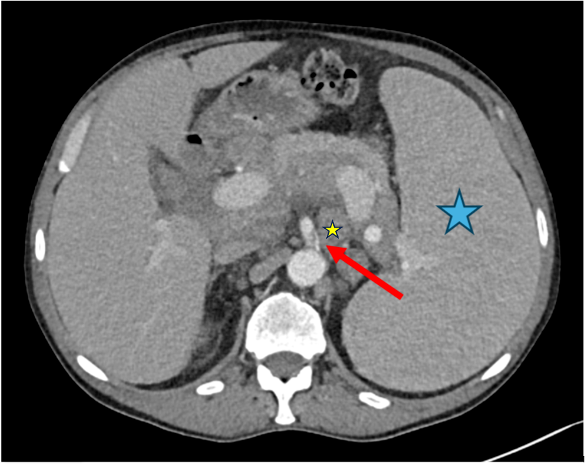

Figure 6.

Case 3, 76-year-old male. Initial chest and abdominal CT to investigate potential infections, including COVID-19 findings, revealed no infectious source. However, there was strong suspicion for metastasized carcinoma: (a) Wall thickening of a urachal remnant raised concern for urachal carcinoma with infiltration of theabdominal wall (red arrow). (b) Enlarged lymph nodes were suspicious for lymph node metastases (red arrow). (c) A peritoneal soft tissue mass suggested peritoneal metastasis (red arrow). (d) A solid pulmonary nodule in the lung raised concern for lung metastases (red arrow). (e) Multiple sclerotic lesions in the spine were indicative of osseous metastasis (red arrow). Histopathological examination following surgical intervention confirmed the diagnosis of metastasized sigmoid carcinoma.